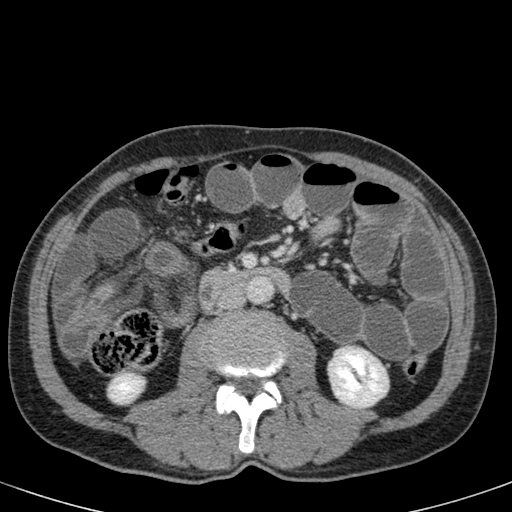

Ca lâm sàng bên trái cho thấy một bệnh nhân khác bị tắc ruột dạng quai kín.

Mặc dù các mạch máu ngấm thuốc tốt, nhưng dường như thành ruột không ngấm thuốc.

Các dấu hiệu thiếu máu cục bộ khác trong ca này bao gồm phù nề mạc treo và dày thành ruột.

Ruột bị nhồi máu được phát hiện trong quá trình phẫu thuật.

Nếu quai kín dài hơn và định hướng vuông góc với mặt phẳng cắt, chúng ta sẽ thấy một cụm quai ruột như trong ca lâm sàng bên trái.

Đôi khi điều này khó nhận biết chỉ trên các lát cắt ngang và các tái tạo mặt phẳng coronal hoặc sagittal có thể hữu ích.

Trong ca này, cũng có phù nề mạc treo và cổ